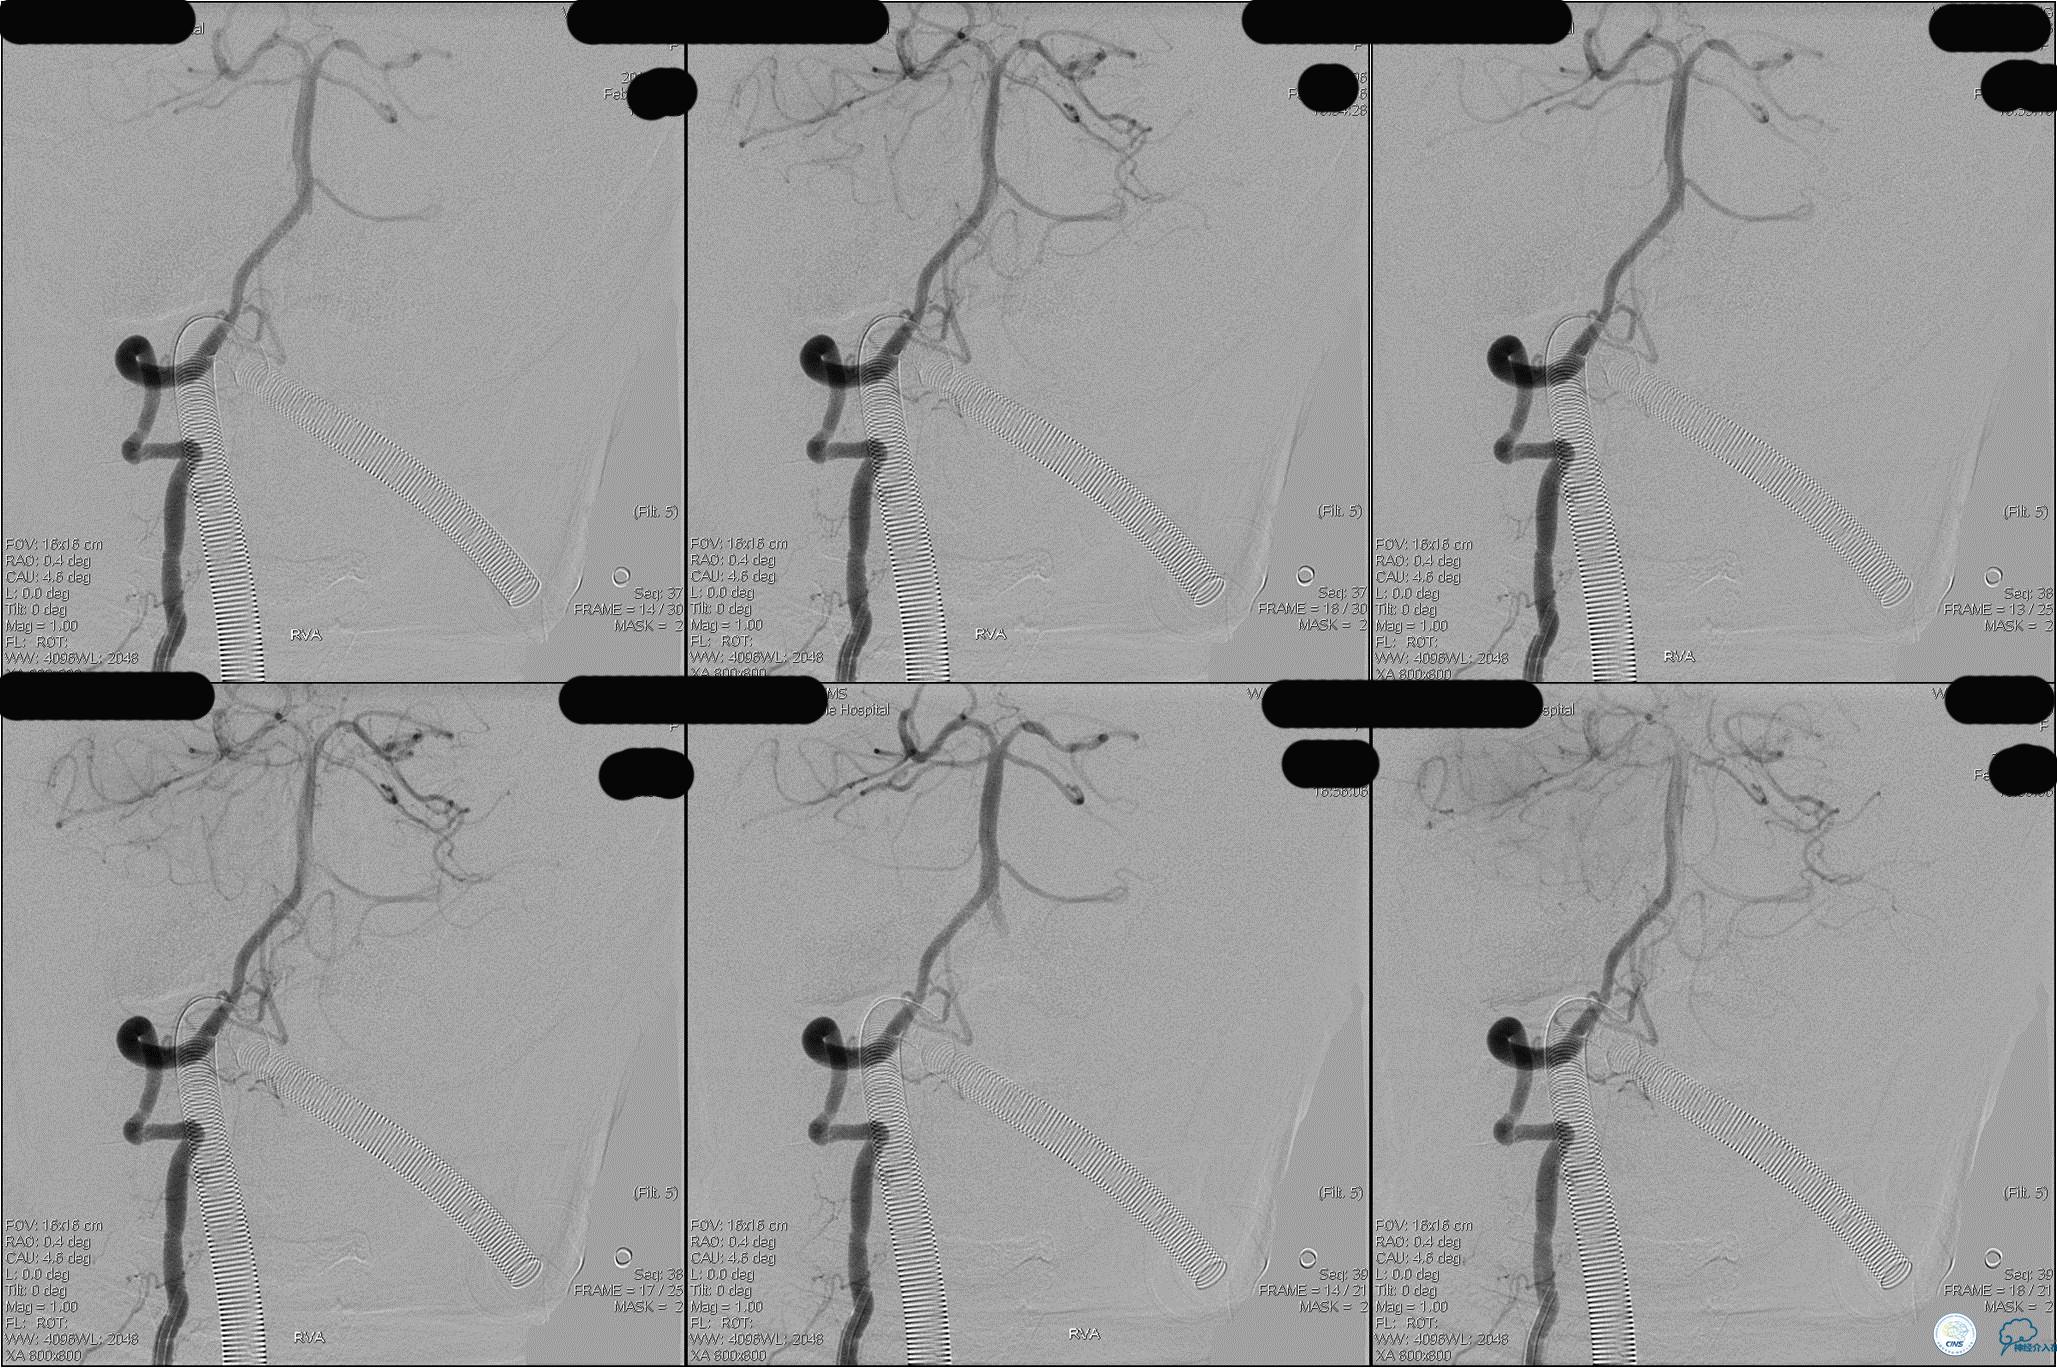

》DSA资料(第3次取栓)

第3次取出血栓

》DSA资料(第3次取栓后,发病10h)

》DSA资料(观察30min后,左椎造影)